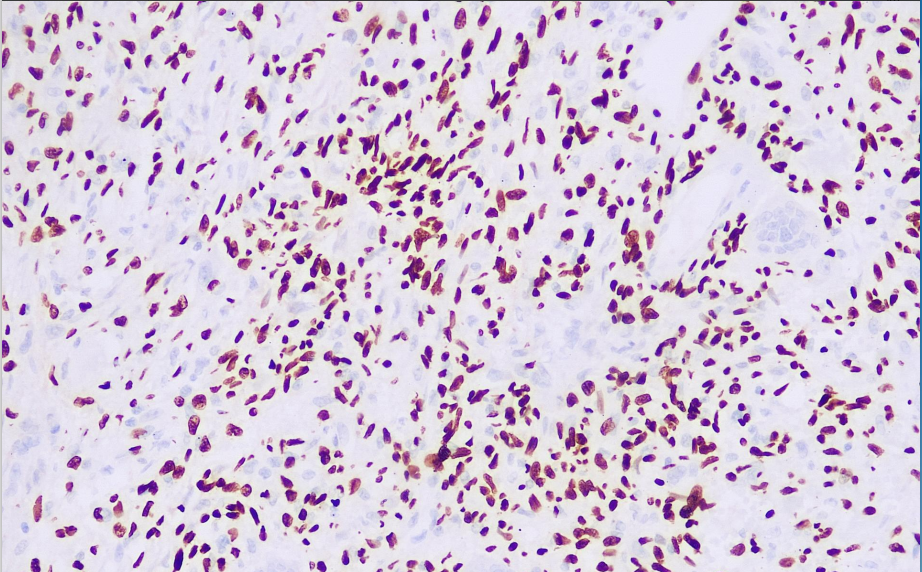

Positive control: osteoblastoma

Giant cell tumor of bone (GCTB) is a locally aggressive joint tumor. Research has found that the expression rate of H3.3G34W in GCTB reaches 97.8%. The H3F3A (H3.3) gene mutation includes a glycine 34 substitution, with an incidence rate of up to 96% in GCTB, with most being the p.G34W mutation type, and only a few being G34L, V, or M mutation types. The H3.3G34W antibody exhibits high specificity and sensitivity toward tumors harboring such mutations, making it an highly effective GCTB biomarker.

The H3.3G34W antibody reagent specifically binds to the H3.3G34W molecular antigen. The immunohistochemistry kit containing the H3.3G34W antibody reagent is suitable for the precise diagnosis of giant cell tumor of bone (GCTB) and certain high-grade gliomas in children (such as H3.3G34 mutation types).